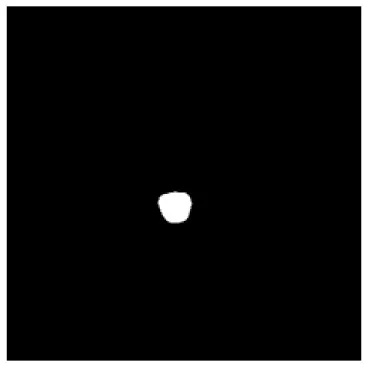

| Input CT image | Organs with manual segmentation | Organ with automatic segmentation | |

| Eye-L | ![]() | ![]() | ![]() |

The result of manual and automatic organ segmentation.